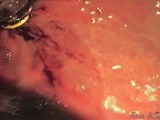

Incisionless Fundoplication - Tiff Procedure

Fundoplication Procedure - Transoral Incisionless Fundoplication

Surgery - Transoral Incisionless Fundoplication